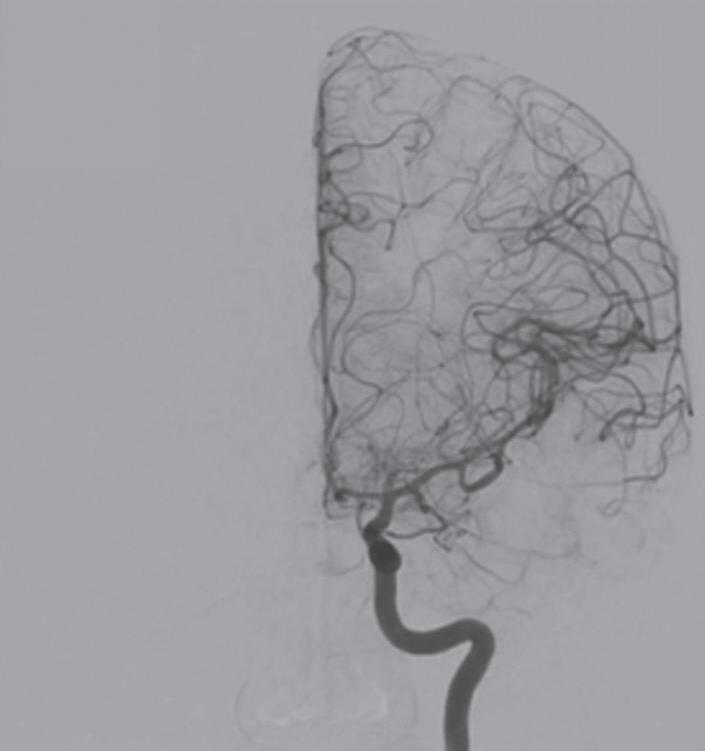

Fig. 1-8. (a-c) RNM T1 com contraste, cortes sagital (a), coronal (b) e axial (c) demonstrando MAV não rota com nidus localizado no lobo occipital à esquerda (setas longas). (d) Arteriografia digital cerebral com injeção de contraste via carótida direita (AP) mostrando a contribuição da carótida direita na irrigação da MAV contralateral. (e,f) Com injeção de contraste via carótida esquerda, em Perfil e AP respectivamente, observa-se nidus compacto nutrido por ramos da artéria cerebral média à esquerda e a veia de drenagem precoce se dirigindo para o seio sagital superior. Projeções em AP (g) e em perfil (h) demonstrando a contribuição do sistema vertebrobasilar por meio de ramos distais da artéria cerebral posterior à esquerda e drenagem para os seios sagital superior e sigmoide à esquerda (setas curtas).